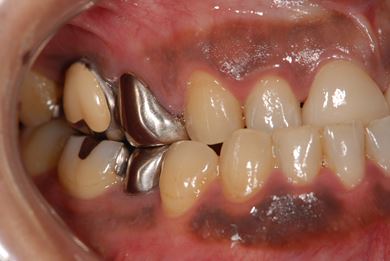

性別/年齢 男性 / 39歳

主訴 前歯のすき間を治したい。

治療方針 上顎前歯をオールセラミッククラウンにて審美的回復を行う。

治療内容 CAD/CAMオールセラミッククラウン2本

治療前

• 治療前